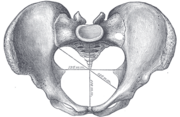

Diameters of pelvic inlet

A distinction is made between the lesser or true pelvis inferior to the terminal line, and the greater or false pelvis above it. The pelvic inlet or superior pelvic aperture, which leads into the lesser pelvis, is bordered by the promontory, the arcuate line of ilium, the iliopubic eminence, the pecten of the pubis, and the upper part of the pubic symphysis. The pelvic outlet or inferior pelvic aperture is the region between the subpubic angle or pubic arch, the ischial tuberosities and the coccyx. [2]

Alternatively, the pelvis is divided into three planes: the inlet, midplane, and outlet.[3]

- The female inlet is larger and oval in shape, while the male sacral promontory projects further (i.e. the male inlet is more heart-shaped).[9]

- The angle between the inferior pubic rami is acute (70 degrees) in men, but obtuse (90–100 degrees) in women. Accordingly, the angle is called subpubic angle in men and pubic arch in women.[9] Additionally, the bones forming the angle/arch are more concave in females but straight in males.[12]

- The distance between the ischia bones is small in males, making the outlet narrow, but large in females, who have a relatively large outlet. The ischial spines and tuberosities are heavier and project farther into the pelvic cavity in males. The greater sciatic notch is wider in females.[12]